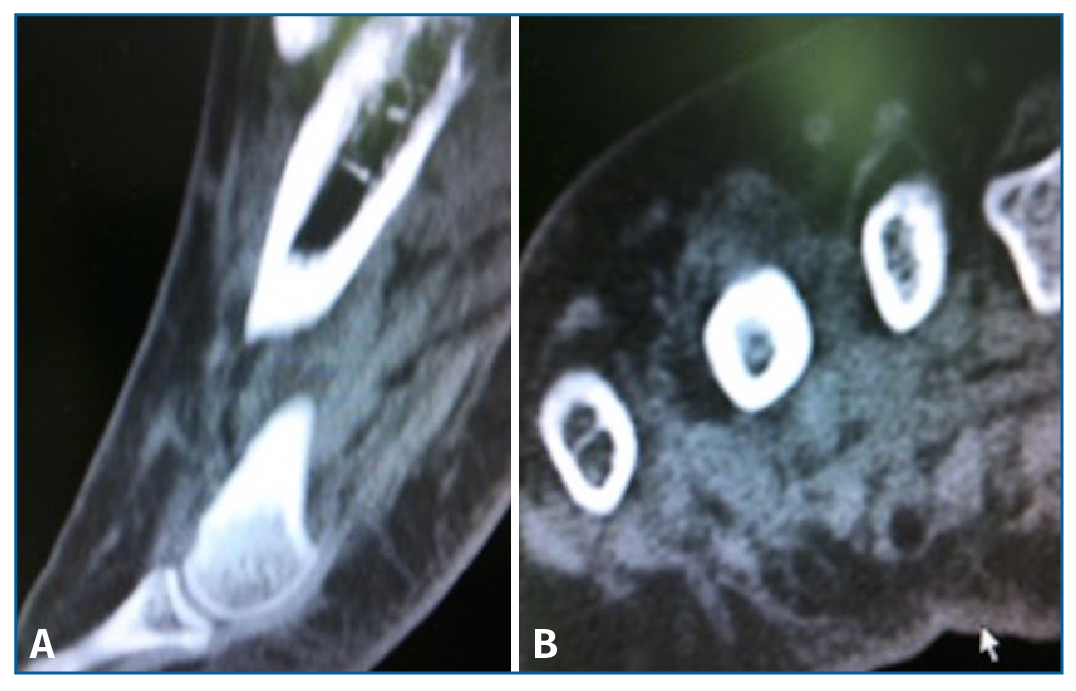

Sin embargo, la tomografía computarizada (TC) solicitada no mostró soluciones de continuidad en la cortical del cuarto metatarsiano (Figura 3).

Figura 3. Tomografía computarizada en corte coronal (A) y axial (B) que no detecta lesión a nivel de la cortical del 4.º metatarsiano.